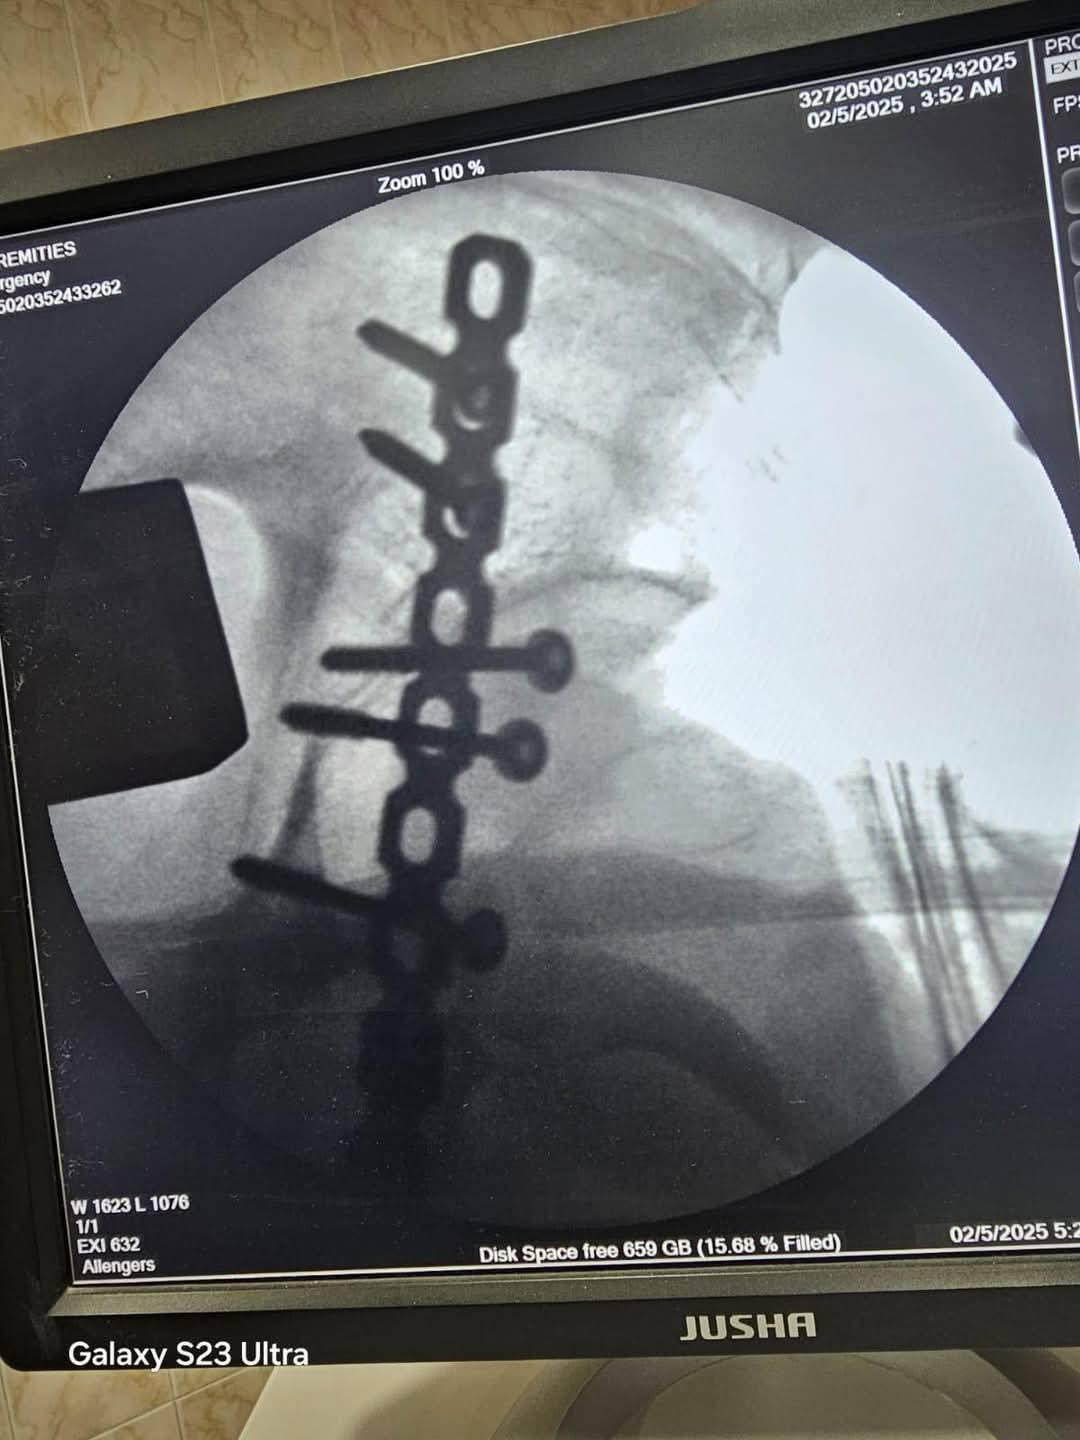

بعد استقرار الحالة، تم تجهيز المريض لإجراء الجراحة العاجلة التي استغرقت قرابة ساعتين ونصف، ونجح خلالها الفريق الطبي في تثبيت الكسور باستخدام شرائح ومسامير، والتأكد من عودة المفصل إلى وضعه الطبيعي.

أُجريت الجراحة تحت إشراف الأستاذ الدكتور الشربيني علي، استشاري ومدرس جراحة العظام، وبمشاركة الدكتور أحمد النعماني، والدكتور أحمد نصار، والدكتور أحمد جمال، وبمساندة فريق التخدير بقيادة الدكتور محمد جمال البلشي، والدكتورة ولاء محمد، إلى جانب أطقم التمريض والتخدير والأشعة والصيدلة.